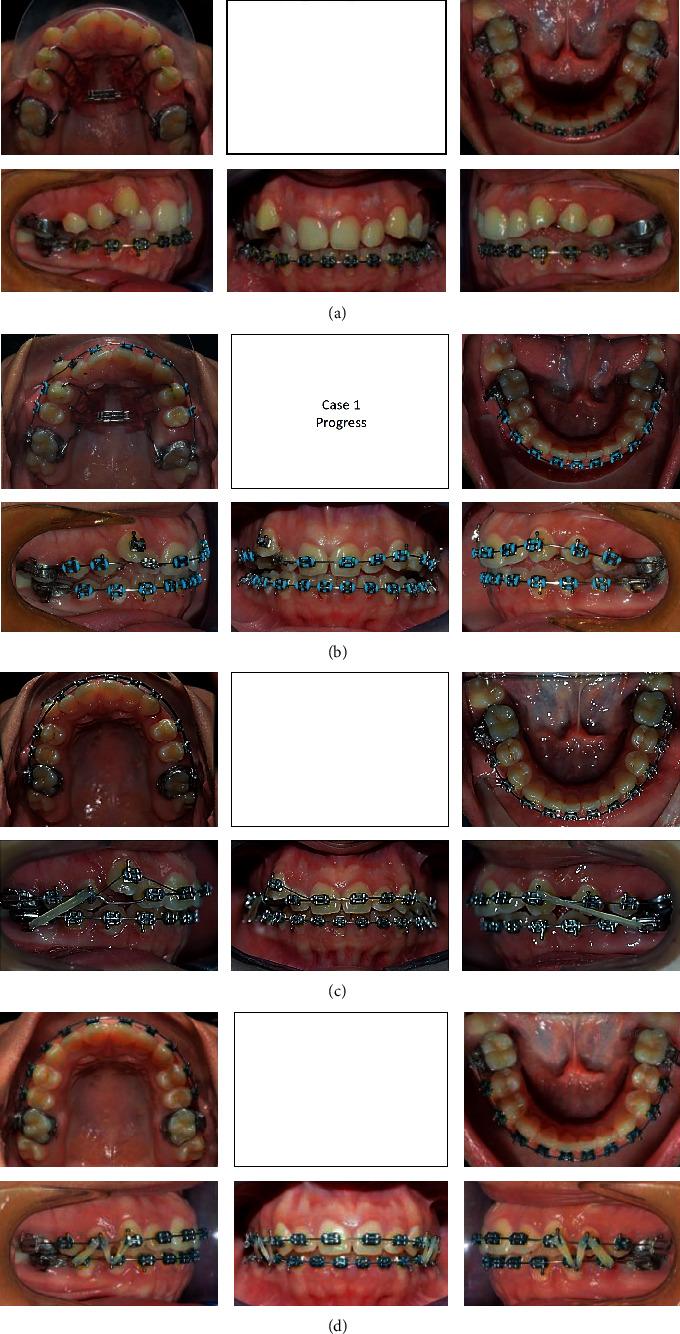

Distalization is a conservative method that is utilized in orthodontics to gain space by moving posterior teeth distally. It may be combined with other space gaining strategies, such as expansion, or can be used alone. Many methods have been used for distalization. These methods differ significantly in their place, whether to be extraoral or intraoral, site of action in upper and/or lower arch, and cooperation needed by the patient if it is removable or fixed. This review illustrates some of the most commonly used methods for distalization with a brief presentation of three cases that incorporated successful distalization techniques.

远中移动是正畸治疗中一种保守的方法,通过将后牙向远中移动来获得间隙。它可以与其他增加间隙的策略(如扩弓)相结合,也可以单独使用。已经有许多方法用于远中移动。这些方法在其位置(口外或口内)、在上颌和/或下颌牙弓的作用部位以及如果是可摘或固定矫治器时患者所需的配合方面有很大差异。本综述阐述了一些最常用的远中移动方法,并简要介绍了三个采用成功远中移动技术的病例。